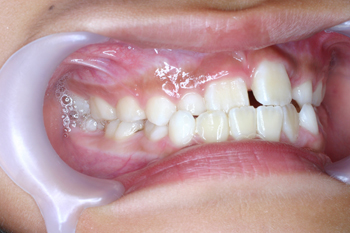

お子様の矯正のご相談に来られました。最初は切端咬合だけだったらしいのですが、反対咬合が酷くなってきたので、子どものうちに治したいということで ご来院されました。

Before

お子様の矯正の場合、お子様自身が痛みや違和感に耐えられなくなるのですが、非常に協力的に治療に取り組んでくれました。